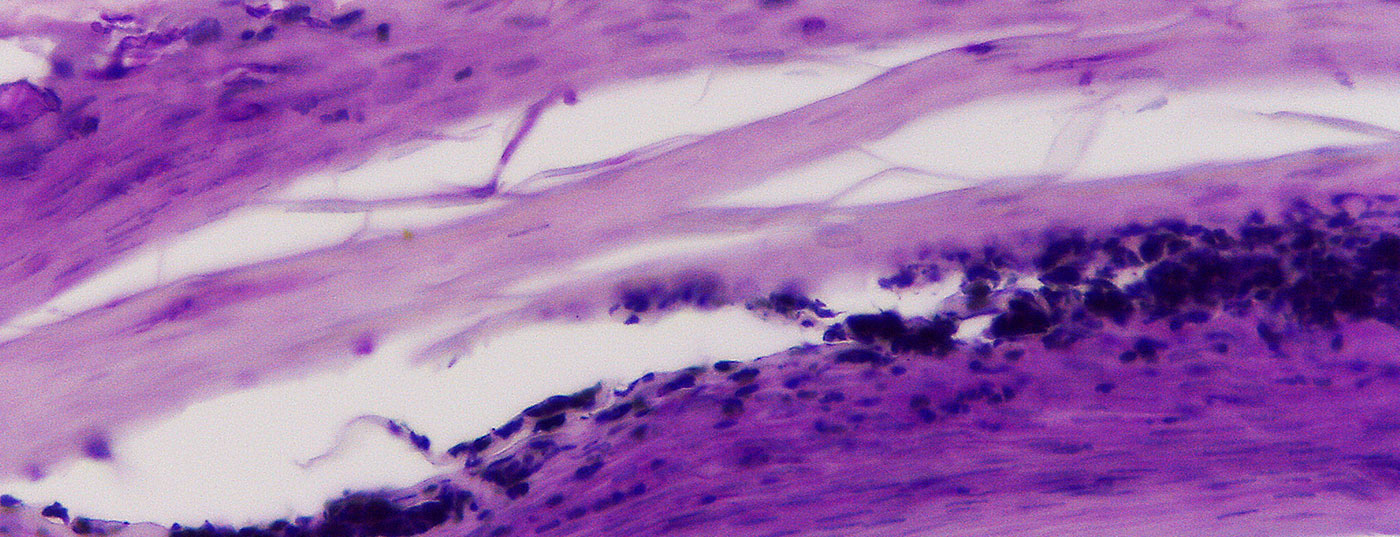

nagelhistologie

• Onychomykosen

Noch immer eine therapeutische Herausforderung

Onychomykosen sind trotz hochwirksamer Antimykotika nach wie vor schwierig zu behandeln. Wie vorgehen bei der häufigsten Nagelerkrankung überhaupt?